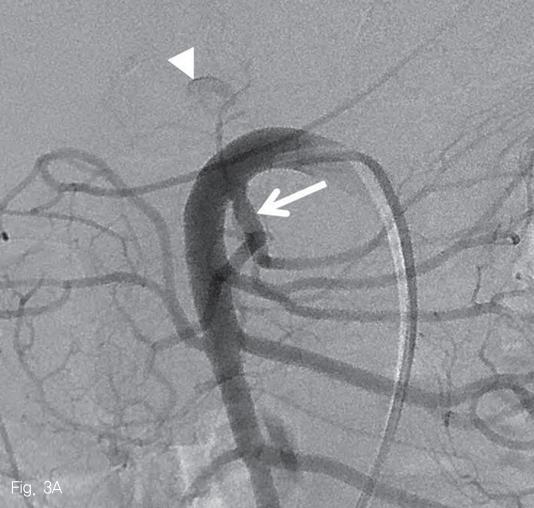

우측 대퇴동맥을 천자하여 5-Fr sheath(Radifocus; Terumo, Tokyo, Japan)를 삽입한 뒤, 5-Fr Cobra catheter(Cook Medical Inc, Bloomington, USA)를 사용하여 상장간막동맥 조영술을 시행하였다. 중간결장동맥의 근위부에 조영제가 채워지는 낭모양의 가성동맥류가 보였다 (Fig. 3A). 중간결장동맥은 상장간막동맥에서 후방으로 기시하여 5-Fr catheter로 선택하기 어려웠다. 0.035-in shapeable guidewire(Radifocus; Terumo, Tokyo, Japan)를 이용하여 중간결장동맥의 근위부까지 5-Fr catheter로 진입하였다 (Fig. 3B). 2.0-Fr microcatheter (Progreat; Terumo, Tokyo, Japan)를 이용해서 병변 직전까지 초선택하였다 (Fig. 3C). N-butyl-2-cyanoacrylate (Histocryl; B. Braun, Tuttlingen, Germany)과 Lipiodol (Guerbet, Paris, France)을 1:2 비율로 섞은 용액(33% glue)으로 색전술을 시행하였고 가성동맥류는 소실되었다 (Fig. 3D). 시술 직후 환자는 통증을 호소하였지만 곧 호전되었다.

Fig 3A

Arteriogram of superior mesenteric artery (SMA) shows a small pseudoaneurysm originating from the middle colic artery (A-C, arrowheads) which has large angle to backward (A). After the superselection of the bleeding branch (C), embolization with 33% glue was performed without any complication (D).